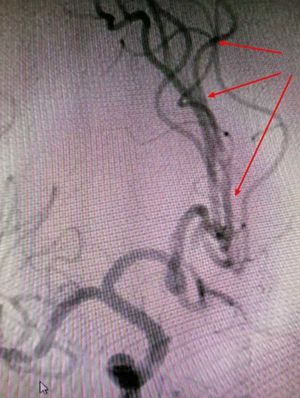

考虑病人发病时间短,立即启动桥接治疗方案。静注rt-PA60mg等治疗,约10分钟后病人肢体肌力逐渐恢复,语言流利,神志清楚,严密观察30分钟,临床症状持续稳定,接着行全脑血管造影。术中发现左侧大脑前动脉已开通,局部A2段狭窄,程度约65%,但向前血流正常,返回病房行正规治疗。

DSA见左侧大脑前动脉开通、向前血流正常